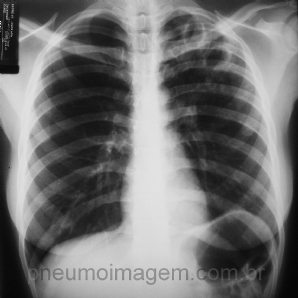

CASO CLÍNICO #23

Homem, 46 anos, apresenta-se com tosse seca há 3 semanas acompanhada por dispneia leve aos esforços. Nega febre e perda de peso. Tabagista por 20 anos/maço. Observe atentamente a radiografia de tórax, faça suas hipóteses diagnósticas e deixe seus comentários. ...